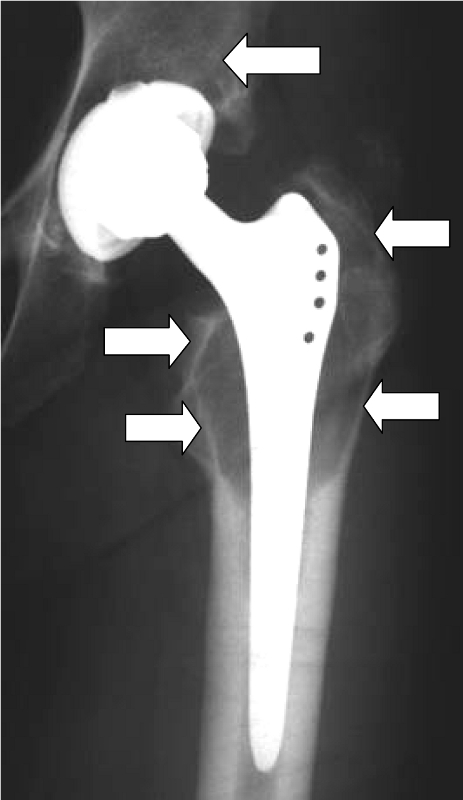

Although statistically only a small proportion of patients develop such hypersensitivity (the figures are less than 1% or between 1 and 4%, depending on the author), we attach great importance to the diagnosis and treatment of hypersensitivity reactions to prostheses in our hospital. If there is a proven allergy to prosthesis components, patients can be fitted with special prostheses made of titanium (hip) or implant coatings (knee). All-ceramic prostheses are currently still undergoing clinical trials. Before considering an implant allergy, however, other causes of the complaints, such as infections, mechanical problems or malpositioning, should be ruled out.